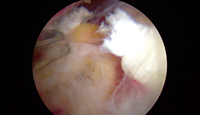

Im Zentrum für Orthopädie und Unfallchirurgie wird die Rekonstruktion der Sehne in fast allen Fällen arthroskopisch durchgeführt. Mit Hilfe von speziellen Fadenankern wird die Sehne am Oberarmkopf refixiert. Verschiedene Nahttechniken werden hierbei angewendet, wobei die verwendete Nahttechnik und die Anzahl der Fadenanker abhängig vom Ausmaß des Sehnenschadens ist.

Wird die Entscheidung zur Operation getroffen, wird in den weitaus meisten Fällen im Rahmen der von uns minimal-invasiv durchgeführten Schulterarthroskopie je nach vorliegendem Gelenkschaden eine Rekonstruktion der Gelenk- und bindegewebigen Anteile mit Hilfe von speziellen Fäden und Ankern mit dem Ziel die Gelenkstabilität wiederherzustellen durchgeführt.